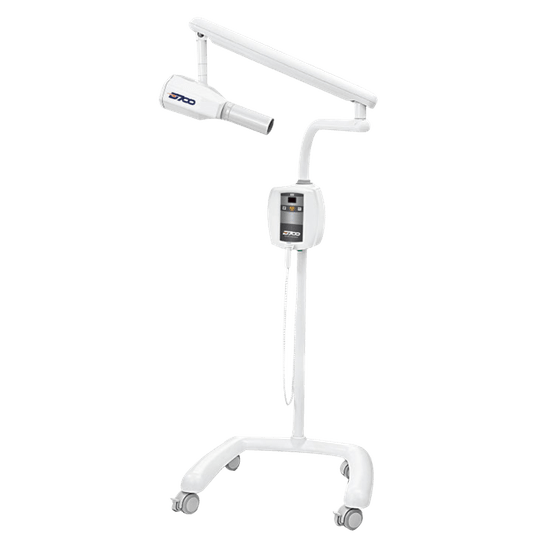

Aparelho Dabi Atlanta Intraoral